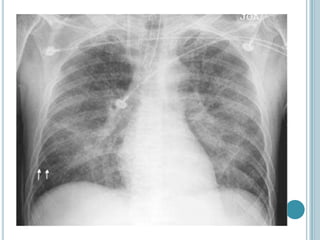

Fundamentalmente clínico. Debe basarse en la historia clínica y

confirmarse con radiografía de tórax.

Puede detectarlo antes de la aparición de signos clínicos.

Rx de Tórax, sin edema. Rx de Tórax, con edema.

DIAGNÓSTICO Fundamentalmente clínico. Debebasarse en la historia clínica y confirmarse con radiografía de tórax. Puede detectarlo antes de la aparición de signos clínicos. Rx de Tórax, sin edema. Rx de Tórax, con edema.